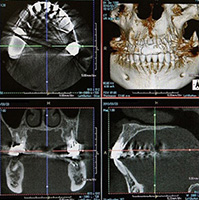

特徴2:CT(三次元立体画像撮影装置)による精密分析

歯周病治療を行う際は、歯や歯ぐきの表面的な状態だけでなく、歯槽骨の状態を正確に把握することが重要です。当院では、三次元立体画像撮影装置(CT)を用いてお口の中を多角的に解析し、歯槽骨の吸収具合や歯の根の形態などを詳細に確認しています。

従来のレントゲンだけでは把握しきれない部位まで精密にチェックすることで、治療計画をより適切に立案することが可能となります。特に、外科的処置が必要な中等度から重度の歯周病においては、骨の高さや厚み、歯根の走行などが治療方針を決める上で大きな要因となります。

CT画像を活用することで、患者さんにもご自身のお口の中の状況を立体的にイメージしていただきやすくなり、治療方針の説明を理解しやすくなります。精密分析を行うことにより、無駄な治療を避け、より安全かつ効果的なアプローチが可能です。